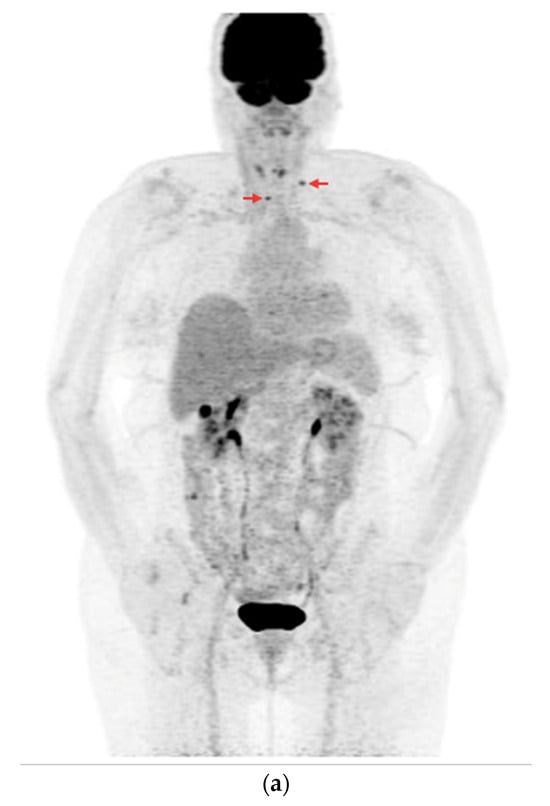

Among the 73 PET/CT examinations with [18F]FDG, 25 examinations were performed without rhTSH stimulation and 48 were performed with rhTSH stimulation. In the subgroup of 25 PET/CT examinations without rhTSH stimulation, in 10 (10/25—40%), positive results of the PET/CT were obtained (Figure 7a,b). The other 15 studies in this subgroup (15/25—60%) were assessed as negative, and no foci of increased [18F]FDG accumulation associated with DTC were found.

Figure 7.

PET/CT with [18F]FDG without rhTSH stimulation (a) Maximum-intensity projection (MIP). An example of accumulation of the [18F]FDG in the lymph nodes: left cervical and right mediastinal (red arrows). (b) Axial fusion projection. An example of accumulation of the [18F]FDG in the right mediastinal lymph node (red arrow).

In the subgroup of 48 PET/CT examinations after rhTSH stimulation, in 18 (18/48—37.5%), positive results were obtained (Figure 8a,b). The other 30 studies in this subgroup (30/48—62.5%) were assessed as negative, and no foci of increased [18F]FDG accumulation associated with DTC were found. The difference in the number of positive results in each subgroup was not statistically significant (p = 0.83).

Figure 8.

PET/CT with [18F]FDG with rhTSH stimulation (a) Maximum-intensity projection (MIP). (b) Axial fusion projection. These show an example of accumulation of the [18F]FDG in the right cervical lymph node (red arrow).